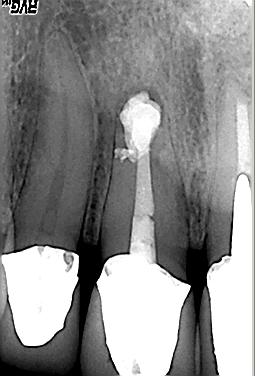

Röntgenologischer Ausgangsbefund im September. 2002 mit alio loco durchgeführter WF. Beide Wurzeln weisen eine apikale Parodontitis auf. Auch in der Furkation ist eine deutliche Resorption zu erkennen. Der Patient hat massive Schmerzen und einen stark herabgesetzten Allgemeinzustand

Röntgenmeßaufnahme

Röntgenmeßaufnahme nach vorgängig durchgeführter endometrischer Längenbestimmung. Nach der ersten Behandlung trat zunächst eine Verbesserung der Symptomatik auf. Nach ca. einer Woche kam es zu einer akuten Exacerbation mit lingualer Abszeßbildung. Der Abszeß wurde inzidiert